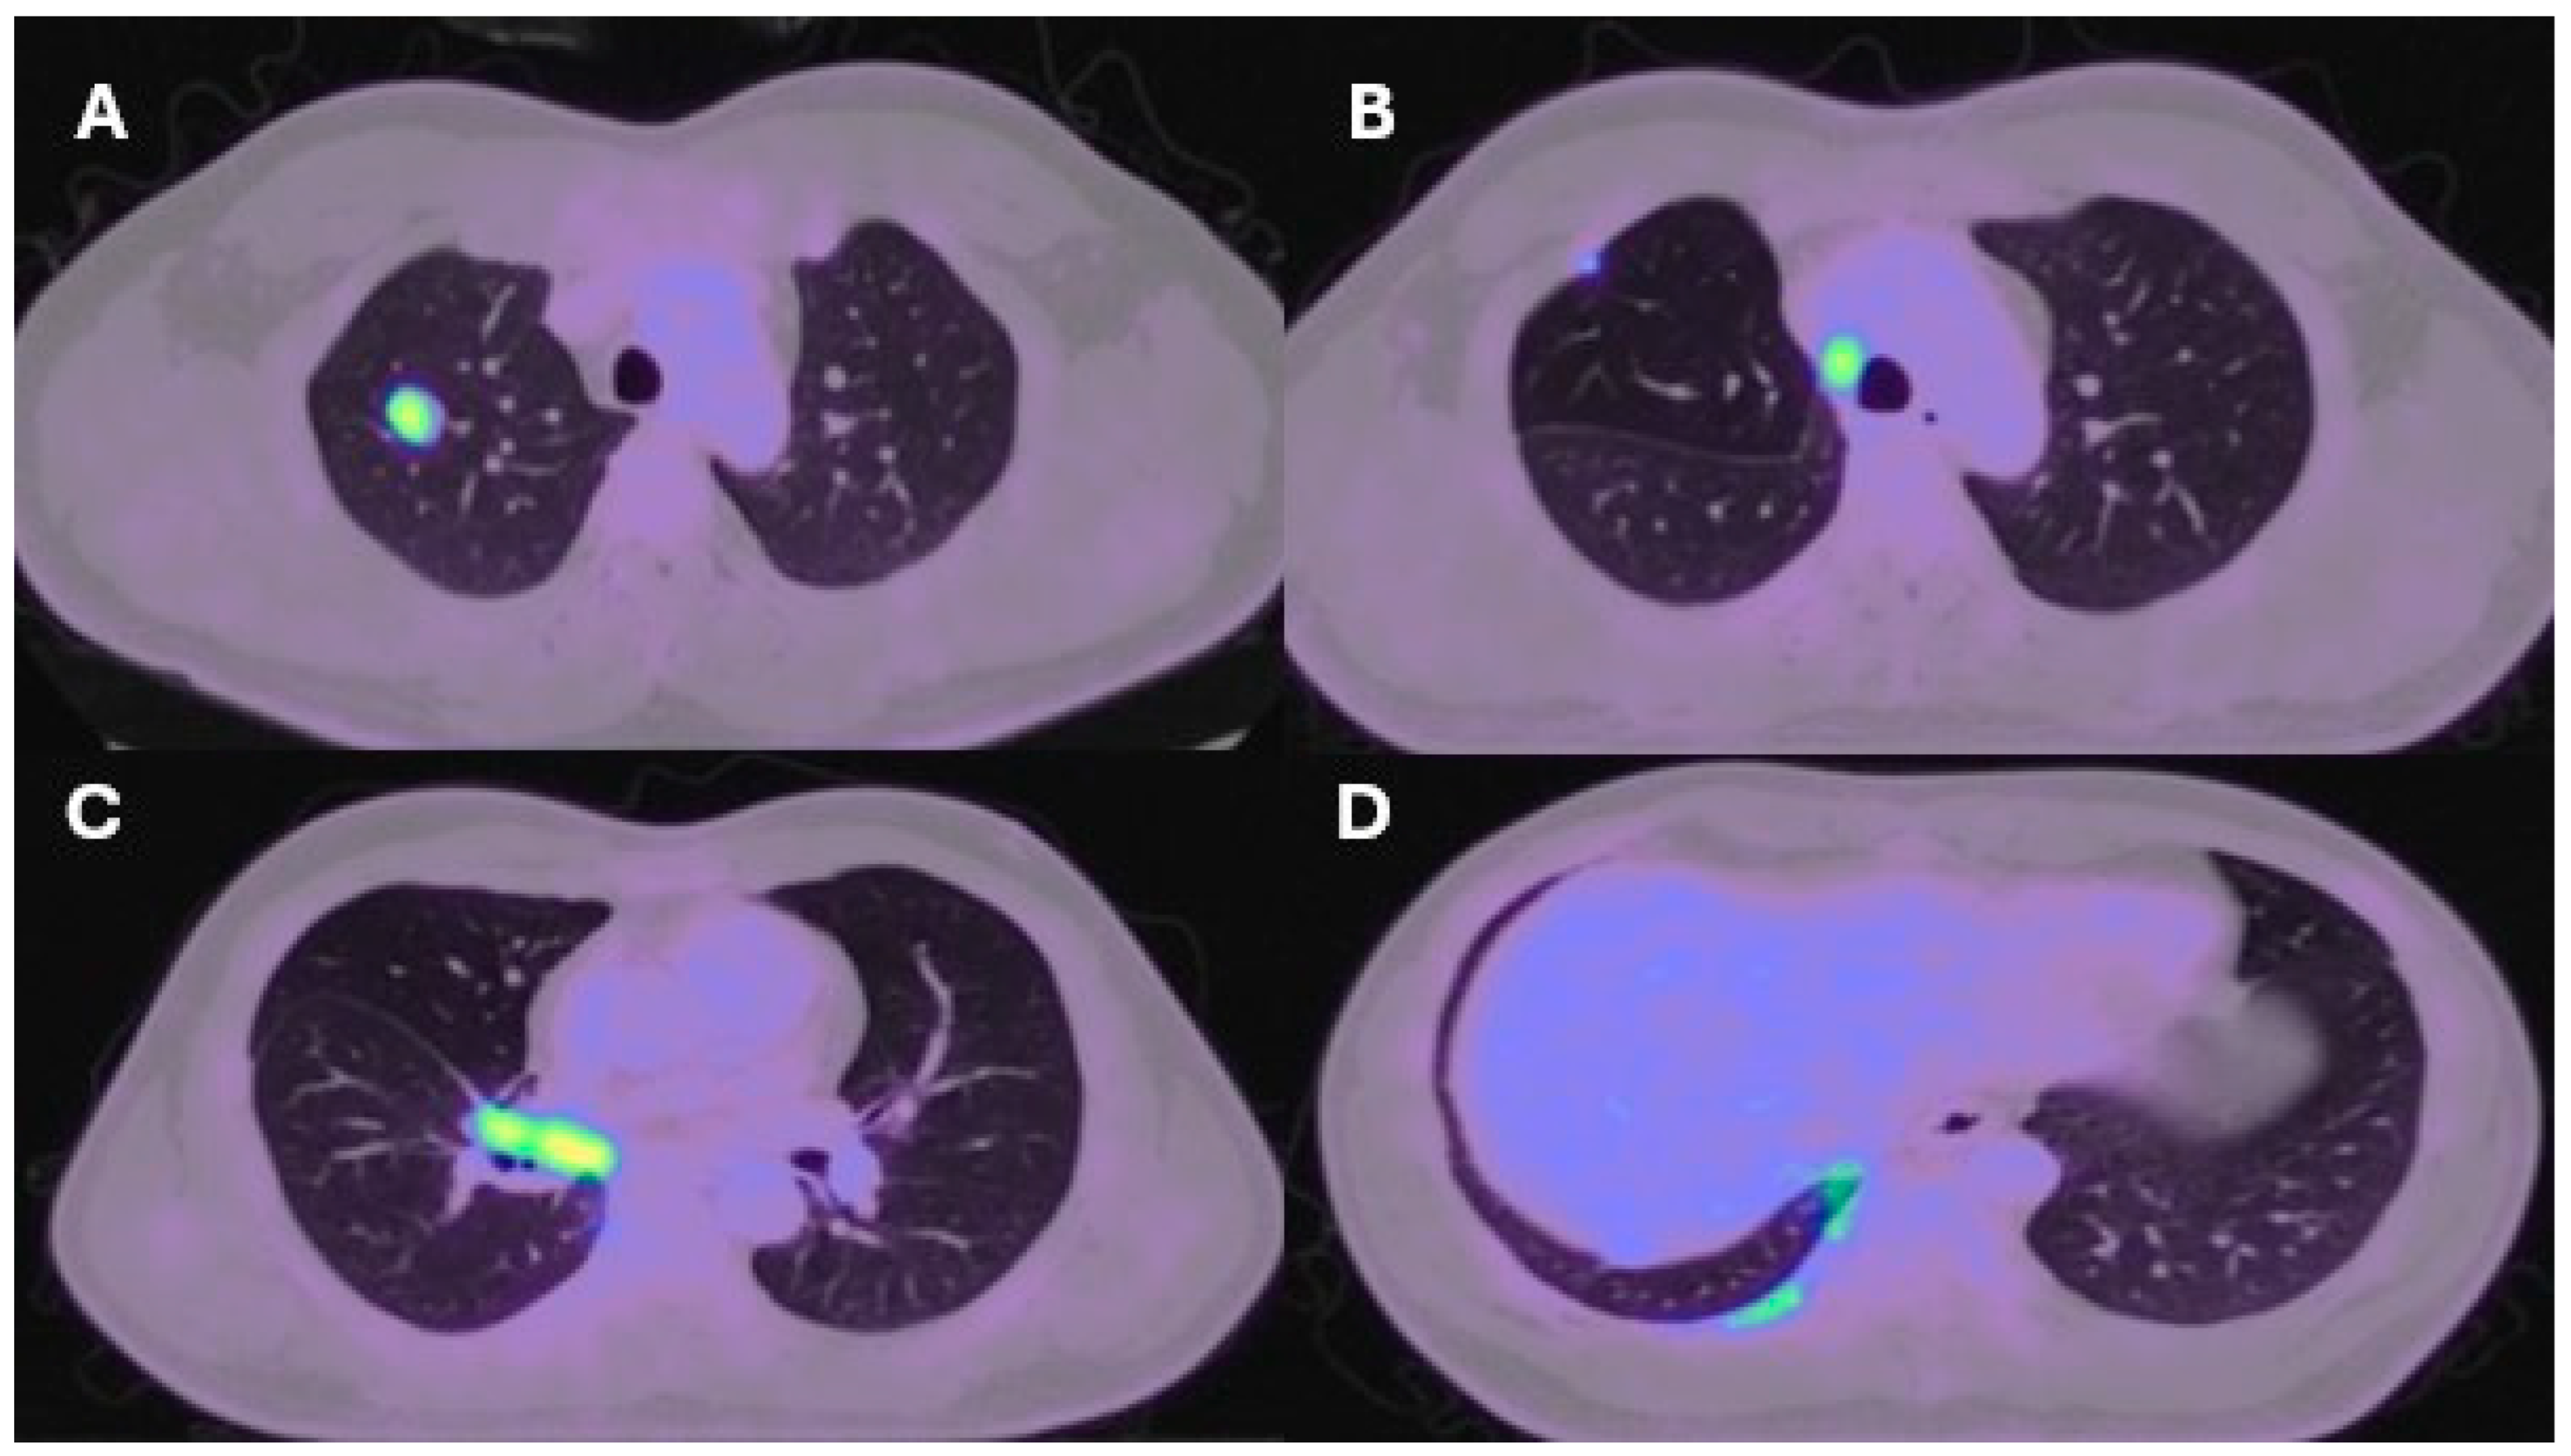

| Lung resection November 2022—Left lower lobectomy + lymph node dissection: pT3pN0 R0 resection. SMARCB1-deficient, PDL1-negative, TTF-1 negative, CD56-positive, cytokeratin positive. Pre-operative CT axial and coronal slices are shown in Figure 2A and Figure 2B, respectively. | Lung resection January 2022—right upper lobectomy + lymph node dissection: pT1cpN0 R0 resection. SMARCB1-deficient, PDL1 negative, TTF-1 negative, CD56-positive, cytokeratin-positive. Pre-operative axial PET slice shown in Figure 3A. |

| Recurrence December 2022—started 4 cycles of Gemcitabine/Cisplatin. Post-operative recurrence demonstrated in PET slices (Figure 2C,D) | Recurrence June 2022—progressive disease noted on CTPA (performed for SOB, pyrexia) at the right hilum, with soft tissue thickening at resection margins. Commenced on Pembrolizumab/Paclitaxel/Cisplatin with systemic intent. Recurrence shown in station 4R (Figure 3B), at the right hilum (Figure 3C) and in the right posterior bony skeleton in ribs 6–9 (Figure 3D). |